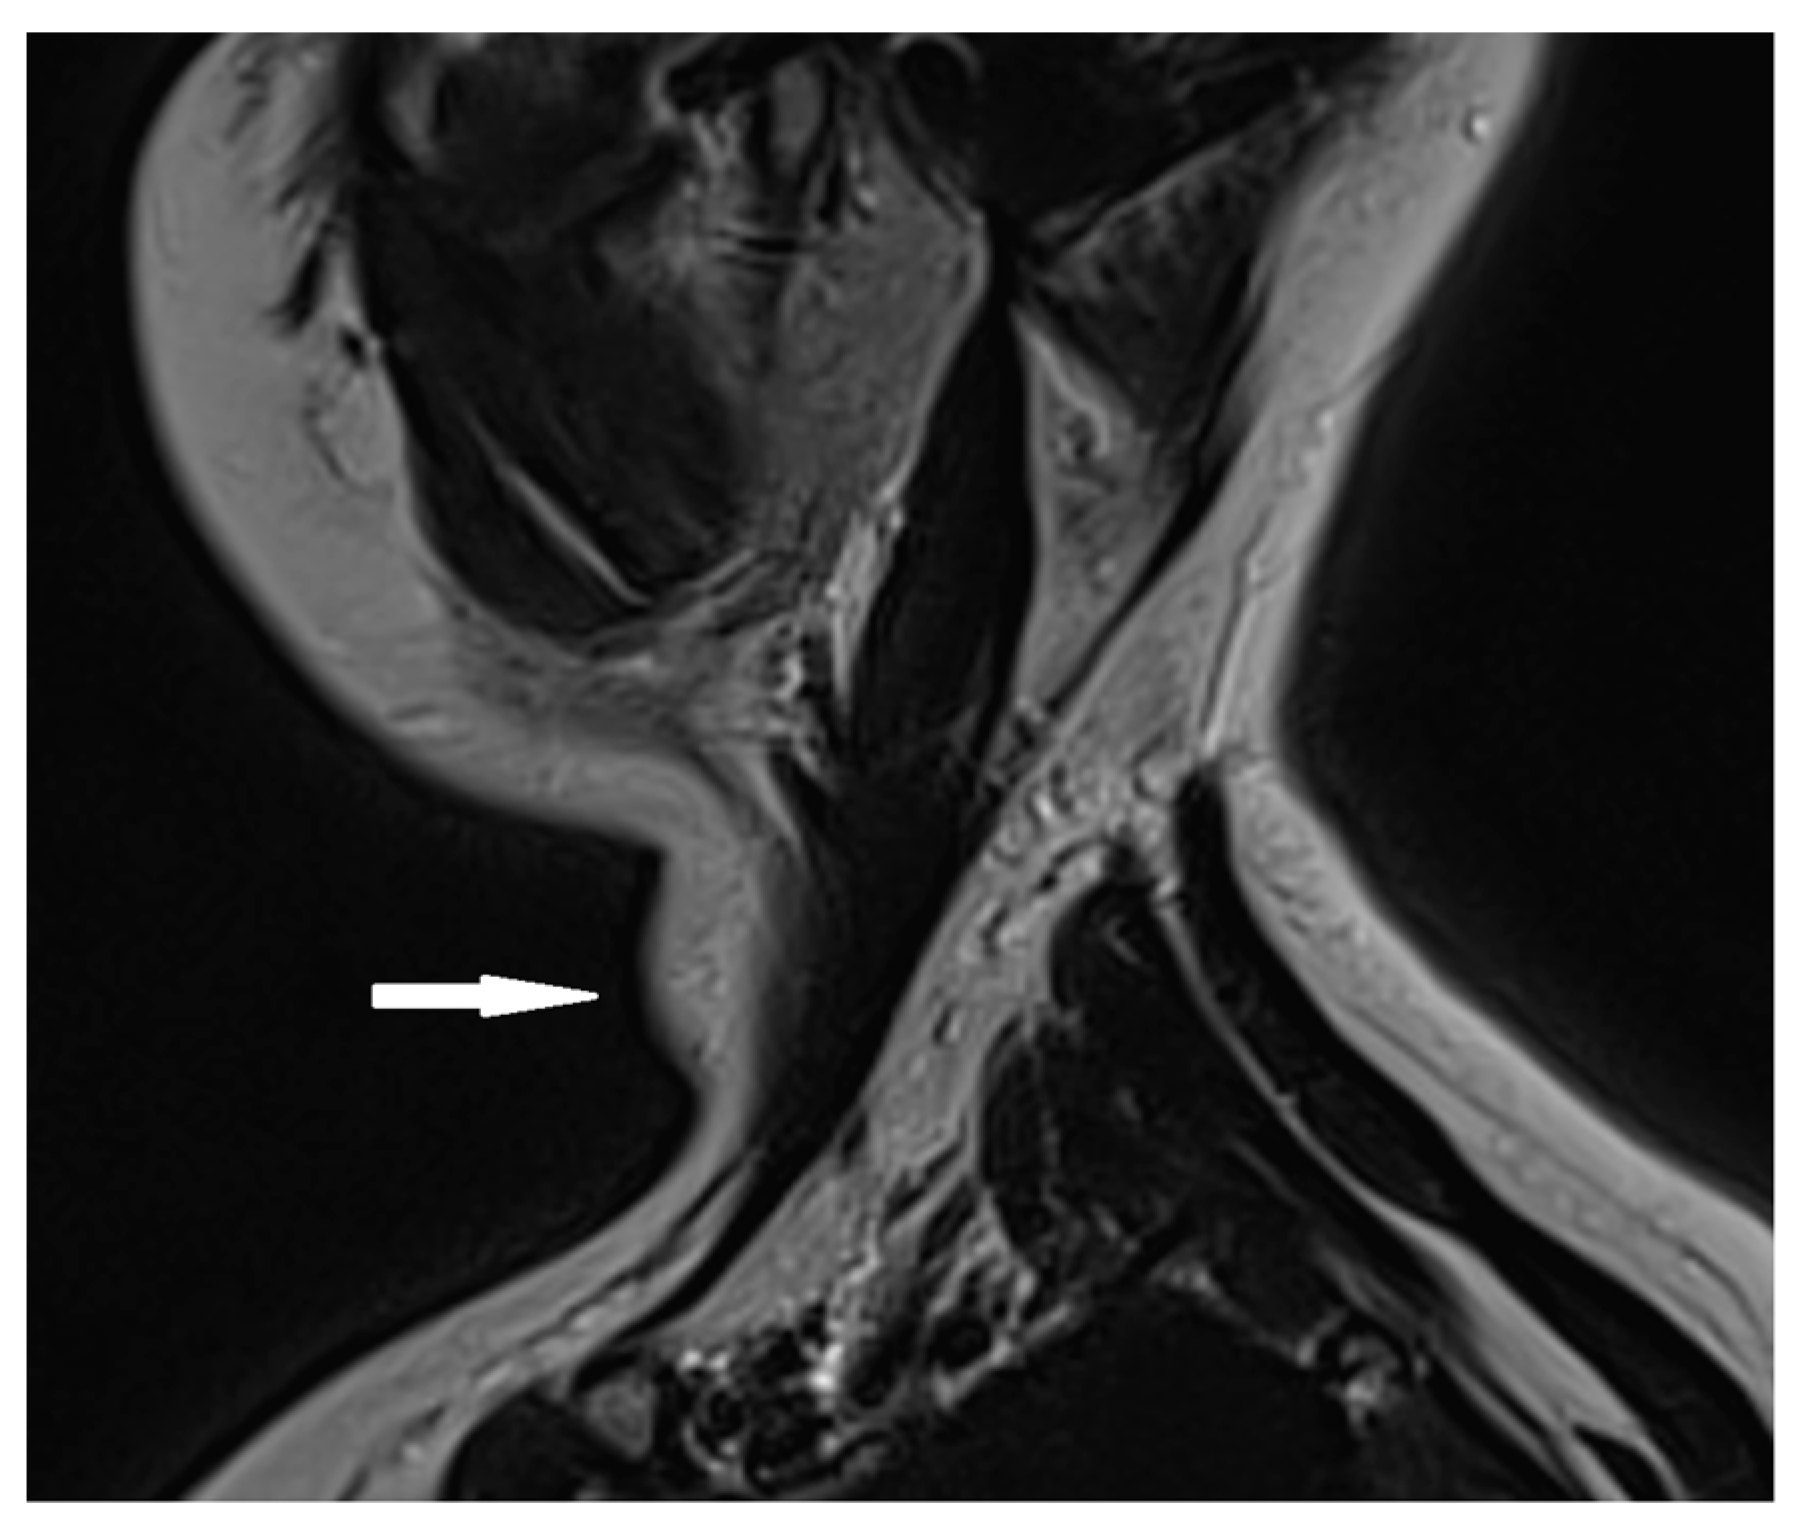

2.3. Biological and Paraclinical Assessment

2.4. Therapeutic Intervention